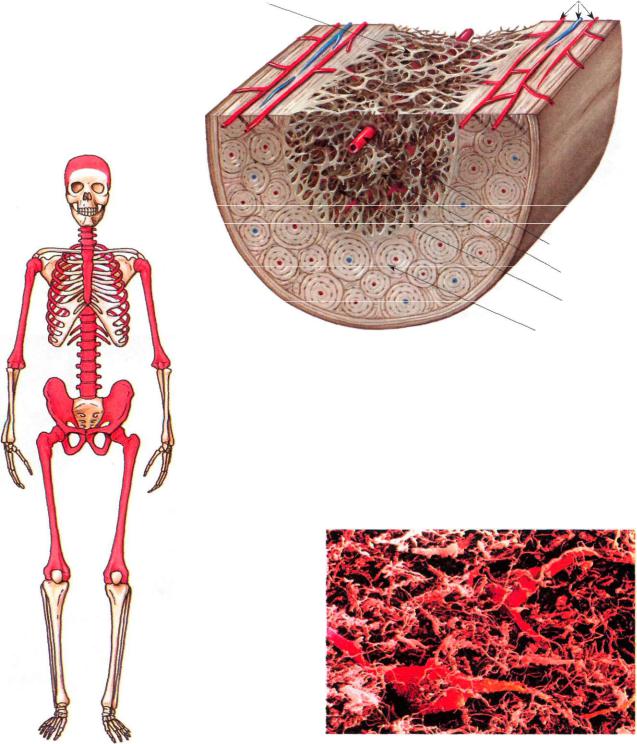

Изучение костного мозга: анатомия и функции